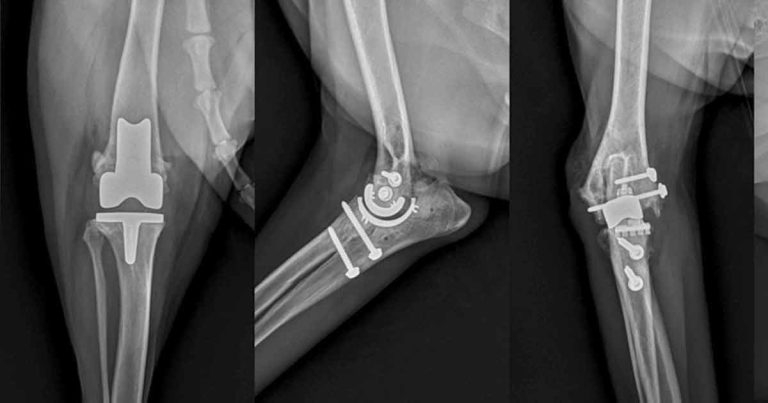

The combined effects of pain, central sensitisation and activity impairment may have negative effects on the affective state, heightening anxiety, depression, sleep impairment9 and cognitive dysfunction, as reported in humans10,11. In the later stages, the pain associated with OA can become severe to the point the patient is a candidate for joint replacement (Figure 1).